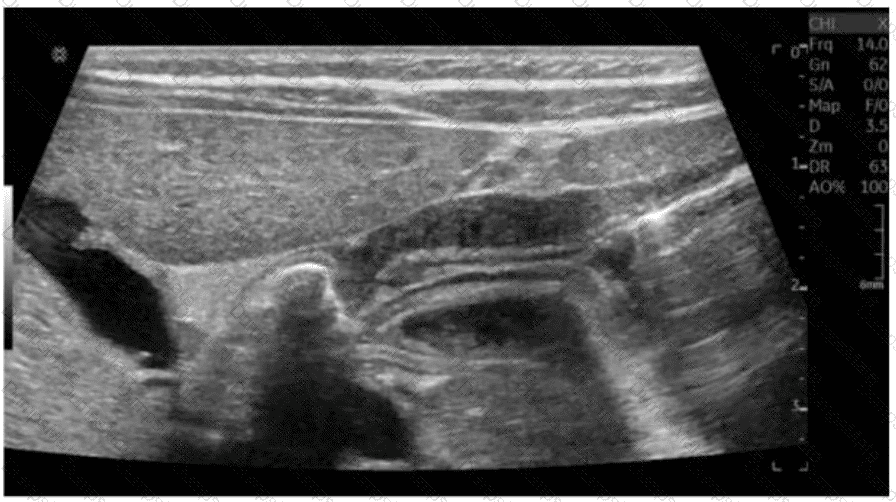

Which condition is most consistent with the sonographic appearance indicated by the arrows on this image obtained post thyroidectomy?

AB-Abdomen Question 6

Options:

A.

Recurring papillary thyroid cancer

B.

Normal postsurgical lymph node

C.

Residual glandular tissue

D.

Reactive lymph node